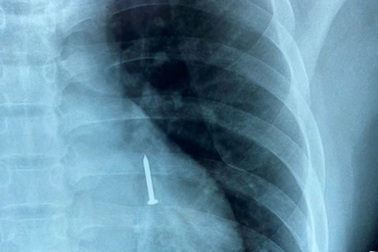

Cứu thợ hồ bị đinh sắt dài 3cm rơi vào phổi khi đang ngậm trong miệngBệnh viện Đà Nẵng cho biết, vừa nội soi gắp thành công cây đinh sắt dài 3 cm nằm trong phế quản cho nam bệnh nhân.